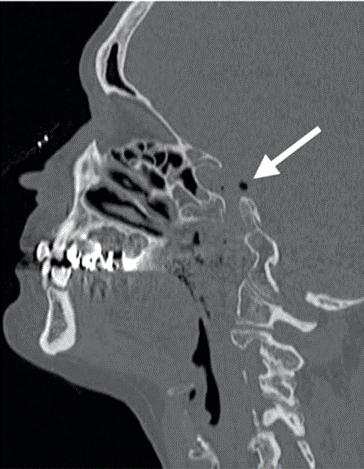

In dit geval heb ik mijn collega die belde voor advies, geadviseerd om contact op te nemen met de implantoloog waar ze mee samenwerkt. De kans dat implantologie op termijn nodig zal zijn, is namelijk heel erg groot. De patiënt kon dezelfde dag nog terecht bij tandarts-implantoloog Tristan Staas. Naast de aanwezige solo is er een CBCT gemaakt (foto 5 en 6). De behandelmogelijkheden zijn hierna uitgebreid besproken.

Er is in deze casus door de implantoloog gekozen om element 21 terug te plaatsen, in de hoop dat het zo lang mogelijk goed blijft gaan. Het stolsel is met een implantaatboor uit de alveole verwijderd en de alveole is iets verruimd. Eigenlijk dezelfde procedure als bij een autotransplantatie. Hierna is het element uitgebreid afgespoeld met fysiologisch zout, teruggeplaatst en aan de spalk bevestigd. Voorheen was,

5. Solo gemaakt meteen na het trauma door de spoeddienst.

6. Screenshot van de CBCT.